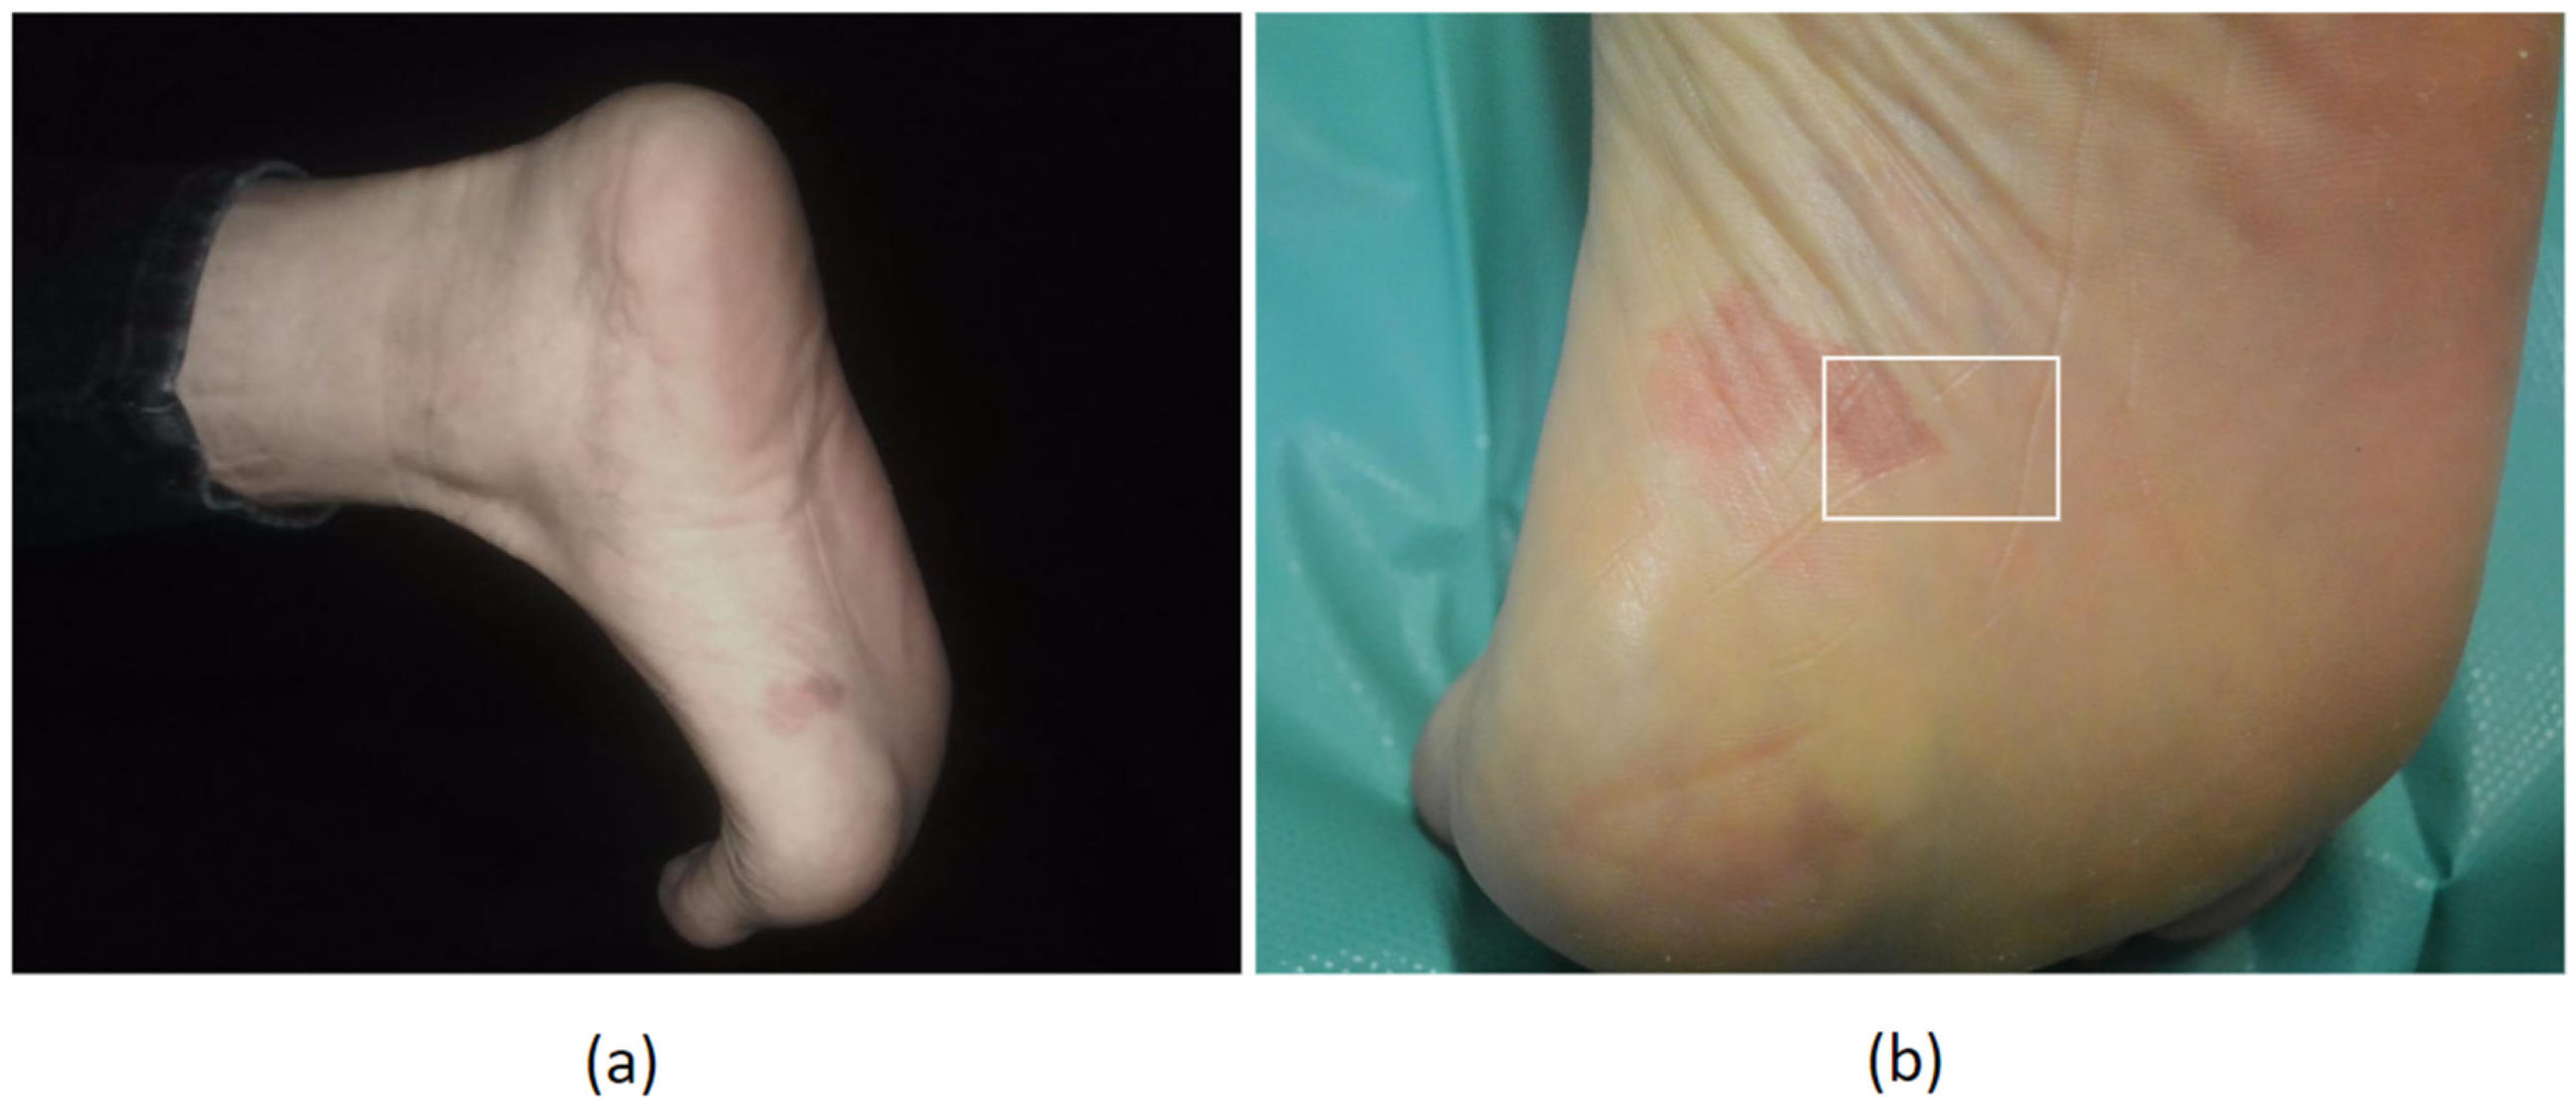

2. Case Report

| 2024 | Our Case | F | 29 | 19 | Left sole |